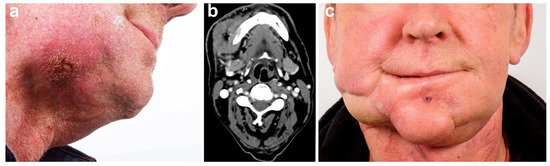

Full-Thickness Tumor Resection of Oral Cancer Involving the Facial Skin—Microsurgical Reconstruction of Extensive Defects after Radical Treatment of Advanced Squamous Cell Carcinoma

2. Results

2.3. Surgical Technique